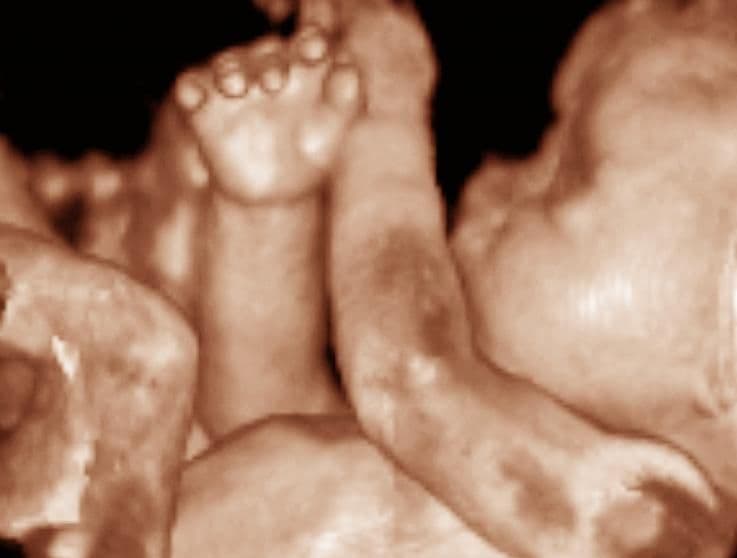

Your baby’s bones are strengthened by the process of ossification in which hard bone is formed from calcium. To meet this increase in demand, you absorb calcium much more readily from your diet.

By this stage of pregnancy, the baby’s humerus in the upper arm, femur in the upper leg, and tibia in the lower leg have undergone this process. As ossification occurs at specific weeks in your pregnancy, ultrasound can use these as markers to estimate the date of the pregnancy, if necessary.

The time at which this ossification occurs may be seen a few days earlier in girls than boys and, interestingly, the patella (knee bone), does not ossify until after birth.